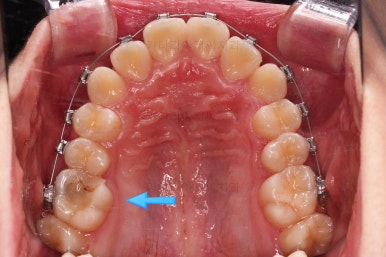

그리고 왼쪽 하단의 사진에 화살표를 보시면, 예전에 신경치료를 해둔 치아인데 어린 나이에 신경치료를 하다보니 크라운으로 치료를 마무리 하지 못했어요.

그래서 기성품을 딸깍 끼워두든지, 위의 화살표 사진처럼 구멍을 떼워두게 돼요.

언제 부러질지 모르는 치아인데, 이번 환자분은 떼워놓은 하방으로 2차적인 충치가 발견되어서 교정치료 마무리와 동시에 빨리 크라운 치료를 해주기로 했어요.

신경치료 되었던 화살표 치아는 그새 더 썩어 일부 부러지기까지 하여 교정 마무리 전까지 버티게끔 임시치아로 감싸주기로 했어요.

입시로 해둔 치아는 잘 버티고 있네요.